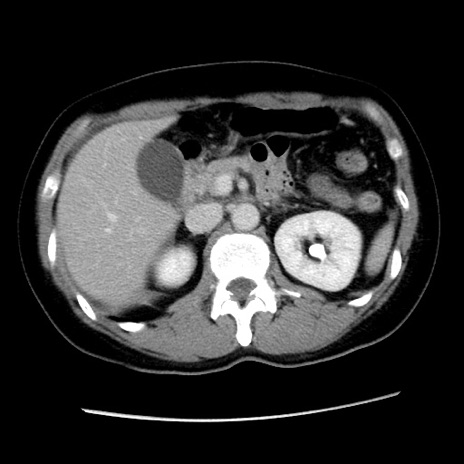

冠状断像

【症例】 50歳代女性

【主訴】 腹痛

【現病歴】前日生レバーを食べた。今朝に排便あり。 昼前に突然発症の腹痛を生じ、当院救急外来を受診した。

【既往歴】 子宮筋腫にてで子宮全摘後

【身体所見】 意識清明、腹部:平坦、軟、下腹部やや左を中心に圧痛・反跳痛あり、筋性防御あり

【データ】WBC 7800、CRP 0.07